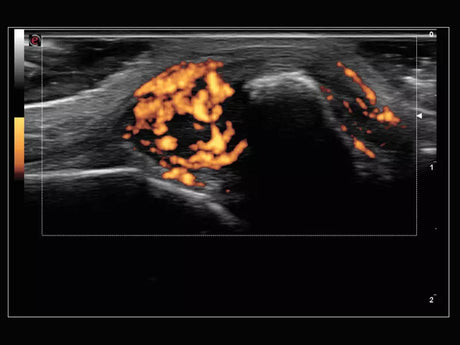

La qualité d’image est au cœur de la philosophie Esaote. Grâce à ses sondes de dernière génération et à son traitement du signal avancé, la marque permet une visualisation fine des structures anatomiques, même les plus profondes. Leurs échographes intègrent des écrans tactiles haute résolution, une interface claire et une connectivité complète, favorisant un flux de travail rapide et efficace.

Les échographes Esaote offrent une restitution d’image d’une grande précision, permettant un diagnostic fiable dans toutes les spécialités. Le traitement numérique optimise le contraste et la netteté, réduisant les artefacts et améliorant la détection des tissus pathologiques. Ces performances sont particulièrement appréciées en gynécologie, où la lisibilité des structures pelviennes ou obstétricales est déterminante.